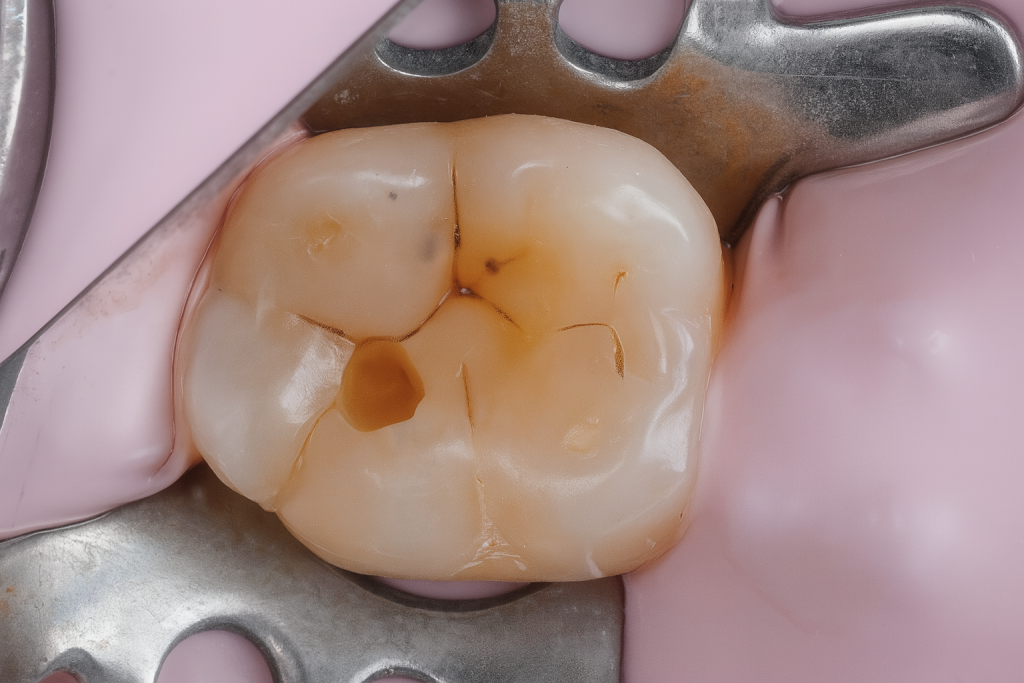

A mandibular first molar presented with localized occlusal caries (Fig 1). Under rubber-dam isolation, conservative cavity preparation was done, preserving pericervical dentin and enamel ridges. The cavity outline followed the carious extension only, minimizing healthy tissue removal.

- Fig 1: Pre-operative occlusal caries on molar.